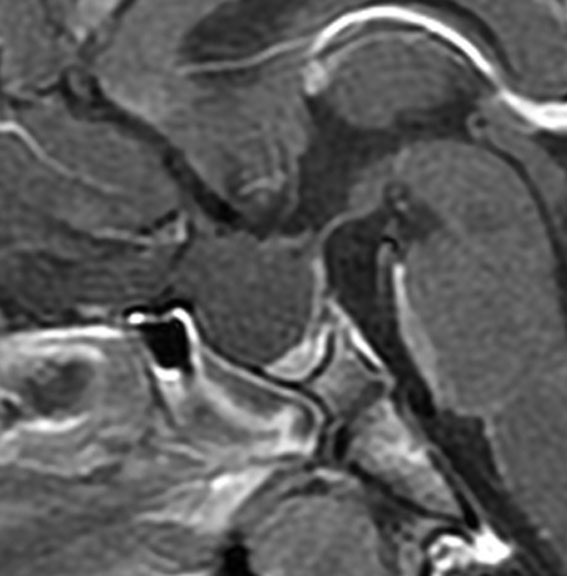

ラトケ嚢胞のMRIです。両耳側半盲という視野の障害(目がみづらい)で発症した女性のものです。左はT2強調画像と言います。右はガドリニウム造影剤を使ったものです。嚢胞のうすい壁だけが見えますが,中身は液体です。鼻孔から入って嚢胞をぷつんとつぶすだけの手術をします。薄い黄色の水のような液体が出ました。

手術後のMRIです。嚢胞はぺしゃんこになって視力は良くなりました。正常の下垂体は残っていてホルモンの障害もありません。